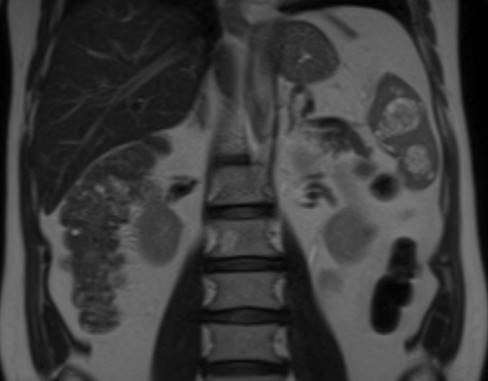

Solicitamos resonancia de abdomen que informó lesiones esplénicas múltiples, desde puntiformes hasta de 35 mm, que realzan heterogéneo con el contraste intravenoso (figura 2) (figura 3).

Figura 2: Resonancia magnética abdomen. Corte coronal. Lesiones esplénicas múltiples.